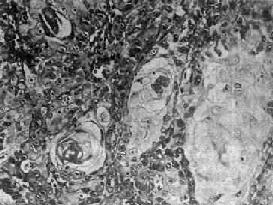

(1)鳞状细胞癌:高分化鳞状细胞癌的癌巢细胞分层明显,可见清晰的棘细胞及细胞内角化,有的还可见角化珠(图9-3)。低分化鳞状细胞癌的癌巢细胞分层多不明显,癌细胞呈多角形、卵圆形、梭形或不规则形,胞浆丰富,境界清楚,少数细胞可见细胞间桥,但无角化现象。

图9-3 鼻咽高分化鳞状细胞癌

癌细胞分化成熟,有角化珠形成